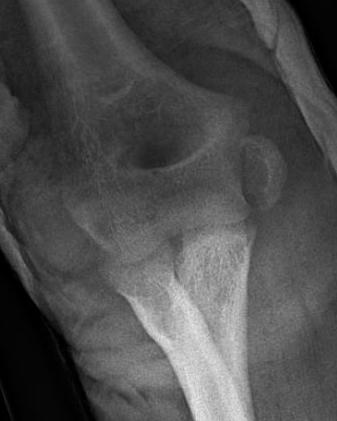

Displaced medial epicondyle fracture

Incarcerated medial epicondyle fracture